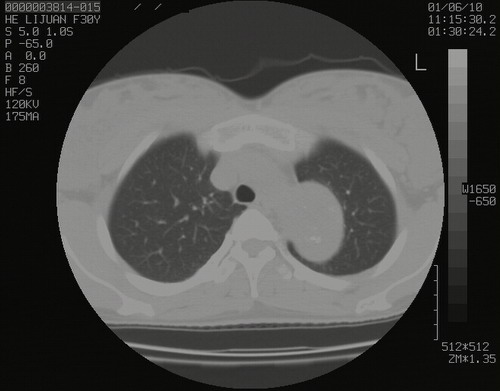

怀孕3个月时(2009-3至4月间),自述突感左侧前后胸疼痛1天,以前胸明显,随后偶感闷痛,余未见异

左肺尖脊柱旁沟肿块,境界清楚,边缘光滑,密度不均,内有多发点片状钙化,考虑良性肿瘤,骨软骨瘤或神经源性肿瘤可能,肺错构瘤不除外。

左后上纵隔见一类圆形肿块影,外侧边界清,密度不均匀,内可见点状钙化影,增强呈不均匀强化,考虑神经源性肿瘤可能。期待病理结果。